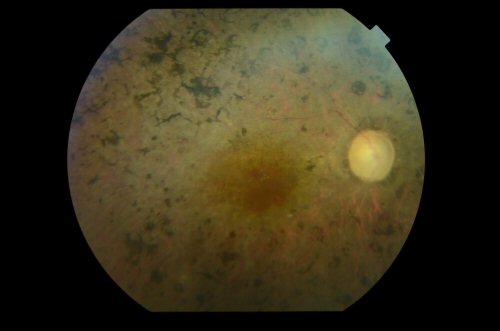

Fondo de ojo de un paciente del presente estudio con retinosis pigmentaria (Foto: Cristina Irigoyen / Hospital Donostia)